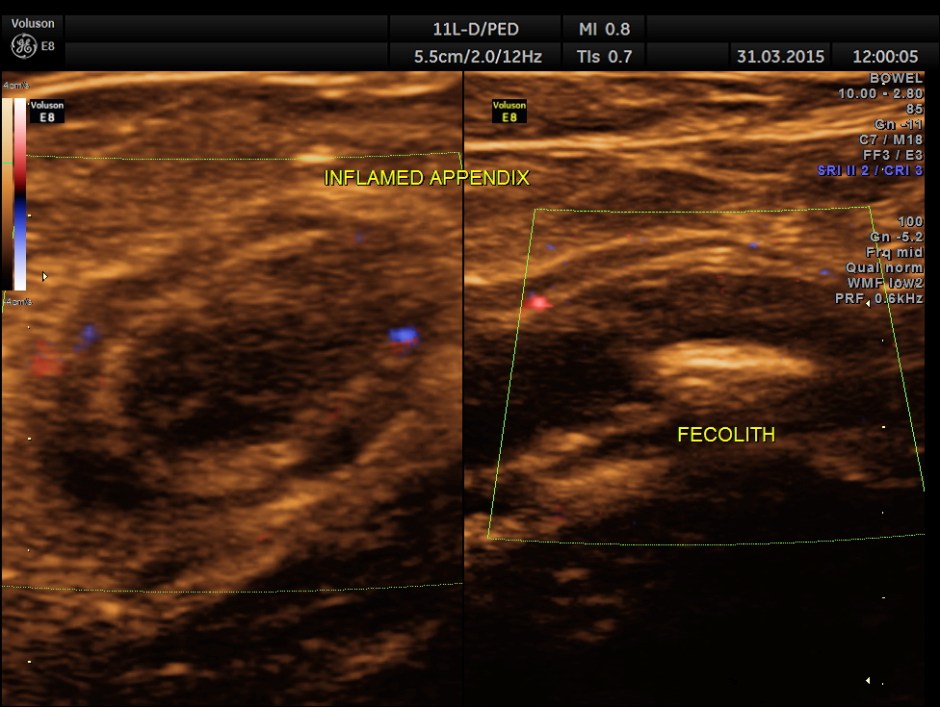

Now this looks more like an inflamed appendix with a prominent fecolith of size 11.4 mms , throwing a shadow.

The following pictures are with a high resolution probe.

The following picture shows the long and short axis views.

Careful attempt to establish any continuity of the dilated ” tube ” to the ureter or dilated pelvis , showed that the dilated structure was separate from the right ureter .

A diagnosis of Acute appendicitis with fecolith was made . CT scan of the abdomen confirmed the diagnosis and after surgery the patient is doing well.